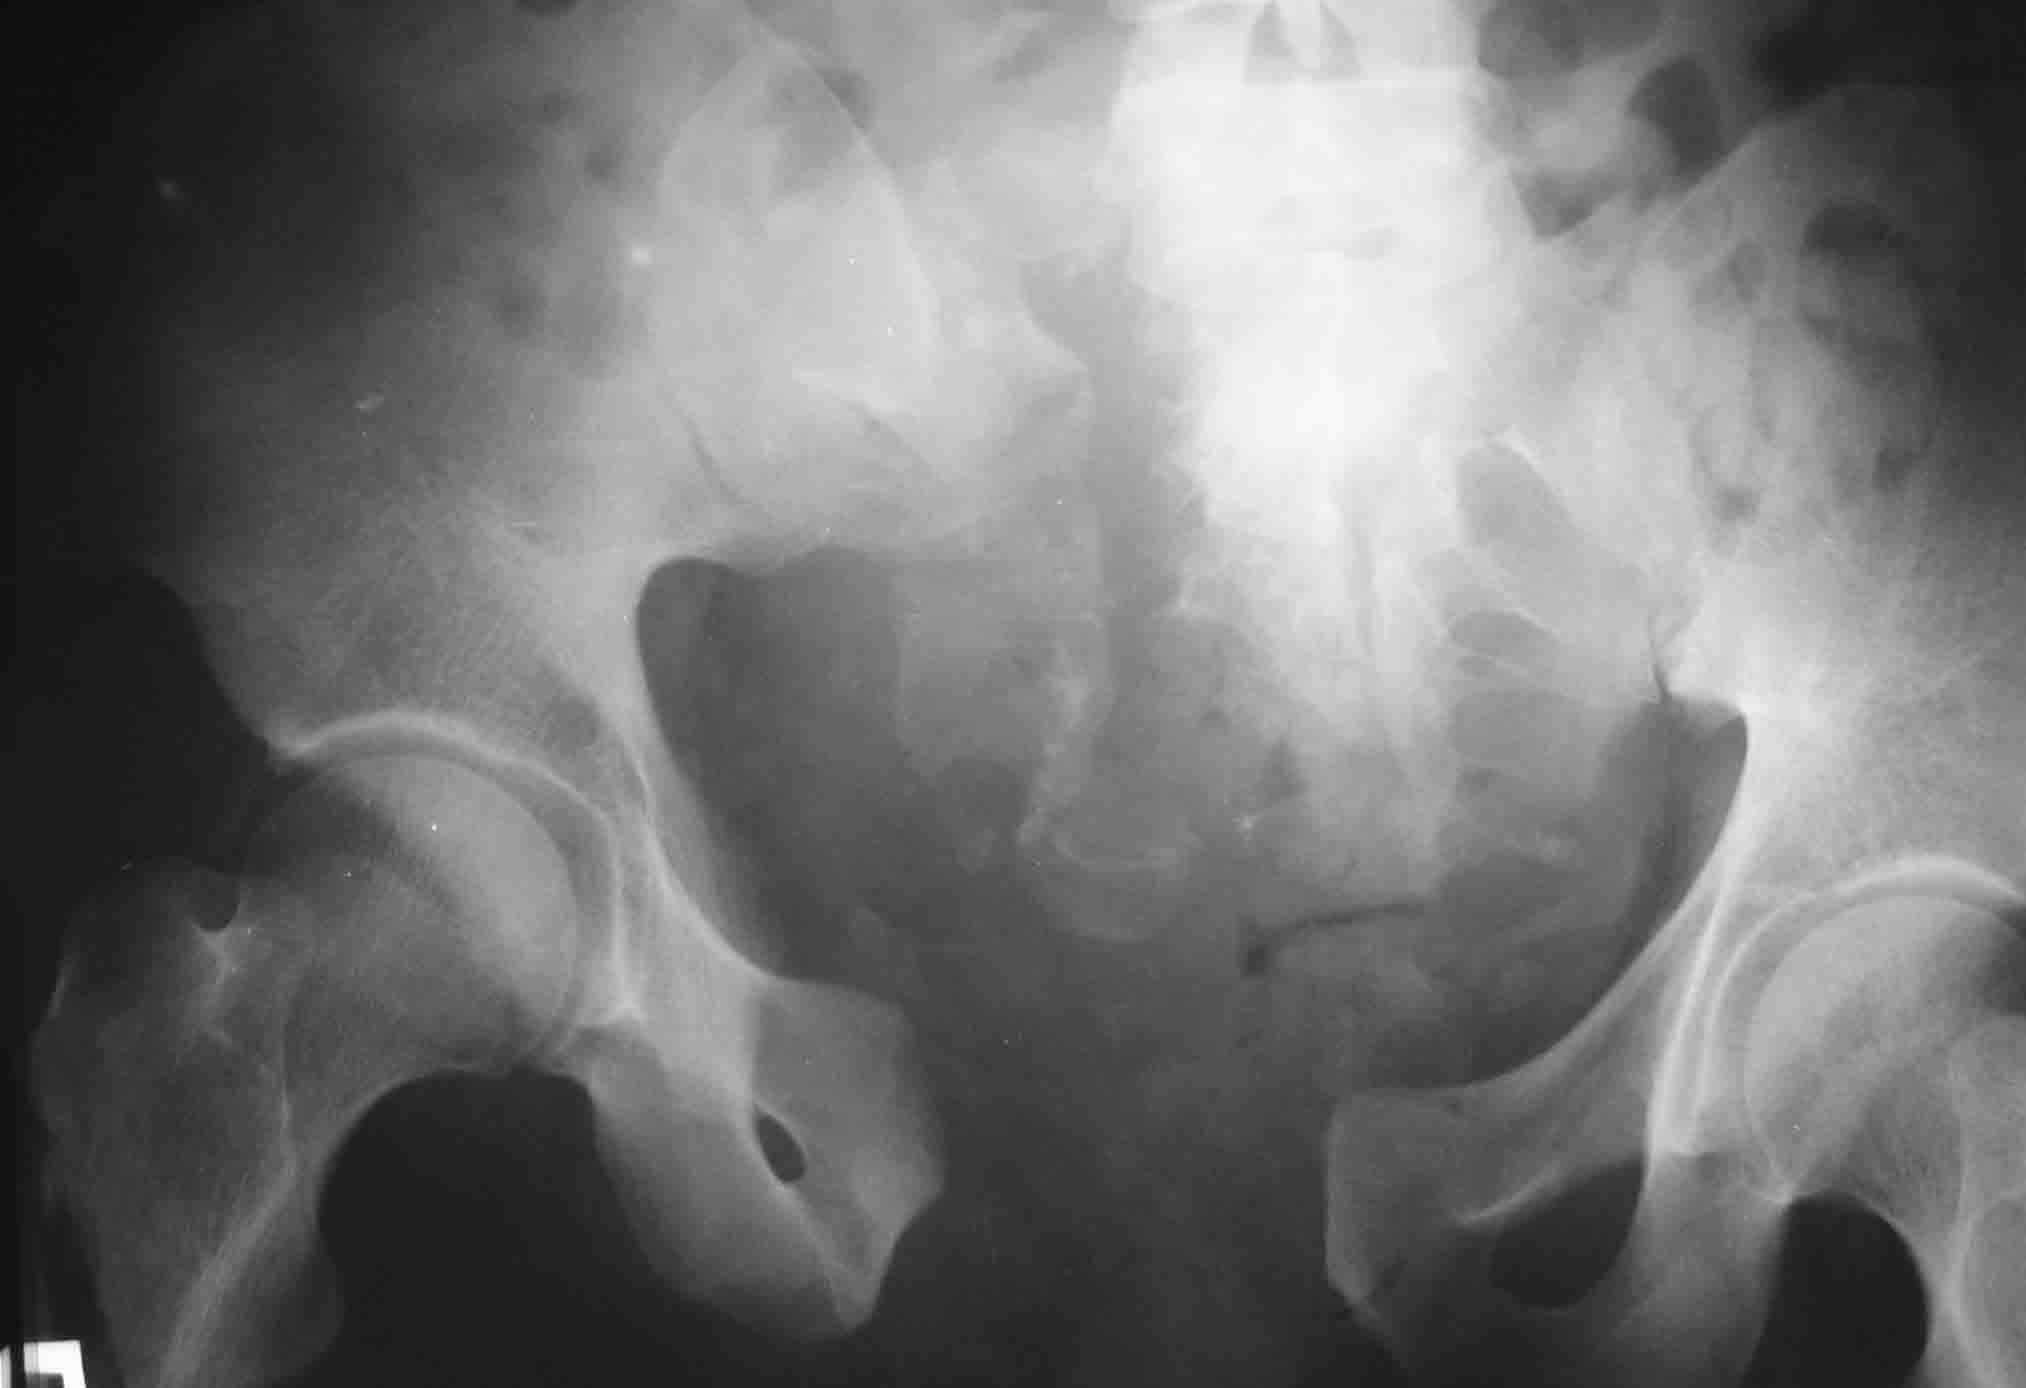

Имя     : 3.jpg

Тип     : application/octet-stream

Размер  : 45174 байтов

Описание: отсутствует

Url     : http://weborto.net:8080/pipermail/ortho/attachments/20071122/26706052/attachment-0007.obj